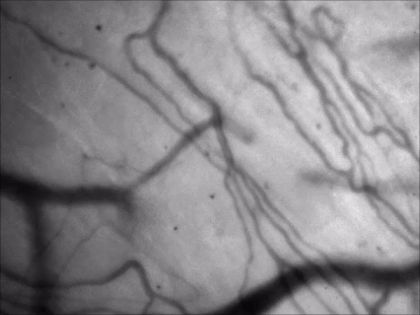

LED подсветка зеленым светом позволяет проводить высококонтрастную визуализацию кровеносных сосудов, используя преимущество, заключающееся в том, что высокое содержание гема в эритроцитах является возбуждаемым в диапазоне спектра 300 – 650 нм. Использование зеленой подсветки помогает перемещаться по поверхности любых органов в условиях in vivo и устанавливать пипетку для ввода или пэтч-клемпинга.

- Высококонтрастная визуализация

- Точное наложение по XYZ между изображениями с камеры и двухфотонного режима

- Определение области хронического сканирования при краниотомии